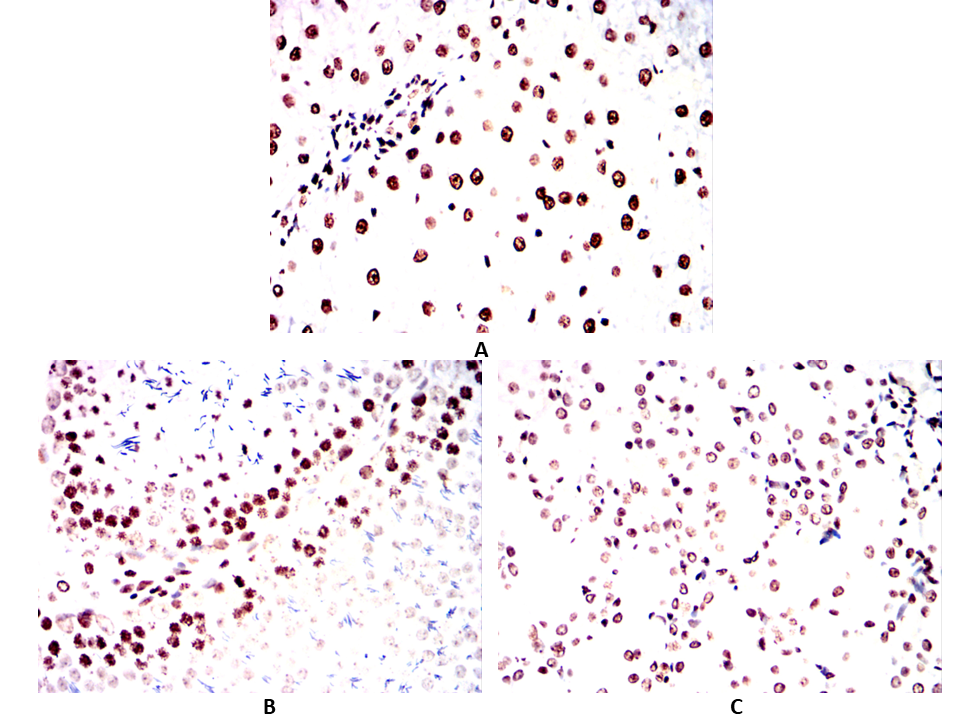

| IHC | 1/100 - 1/500 | Human,Mouse,Rat,Rabbit |

Antibodies targeting p16 are essential tools in both research and diagnostics. Mouse- and human-specific p16 antibodies enable the detection of p16 expression across species, facilitating comparative studies in preclinical models (e.g., murine systems) and human tissues. These antibodies are widely used in techniques such as immunohistochemistry (IHC), Western blotting, and immunofluorescence to assess p16 status in tumors, senescent cells, or disease models. In clinical settings, p16 immunohistochemistry serves as a surrogate marker for high-risk human papillomavirus (HPV) infection in cervical and head/neck cancers, aiding diagnosis and prognosis.